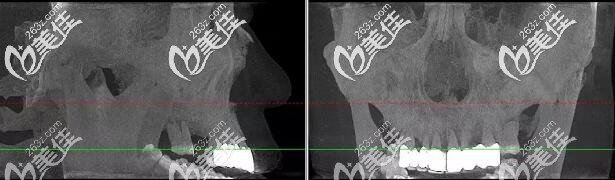

術(shù)前肖先生CBCT口腔影像

術(shù)后肖先生CBCT口腔影像